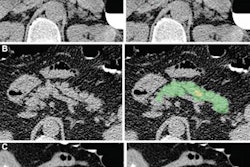

As a result, the researchers sought to utilize a "neural network to connect the codes to the x-ray and convert the images into biomarkers of patients' chronic disease burden," Pyrros said.

Using over 14,000 ambulatory frontal chest x-rays, the multi-institutional team of researchers trained a multitask deep-learning model to predict comorbidities and then associate these findings with self-reported race/ethnicity recorded in the electronic health record (EHR) software.